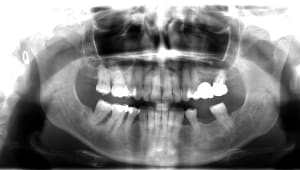

10-07-2025 Panoramique Fin.JPG